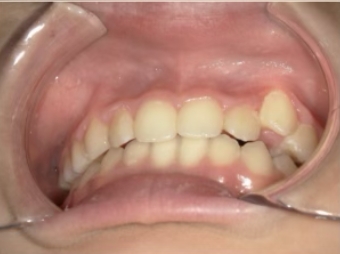

治療前① 小1:6y8m 初診

| カウンセリング・診断結果 | 前歯の生え変わり時期に来院されました。(写真①) 乳歯列期に受け口の既往があり切端咬合になりそうなため、受け口に対する矯正治療の考え方と対処法、当院のコンセプトを説明したところ治療を希望されたので診断を行いました。 診断の結果、上顎骨に対し下顎骨が長く、骨格的な構造も下顎突出型反対咬合(下顎骨が適切な位置よりも前に出ているタイプの受け口)と分かりました。 顔立ちは、中顔面が引っ込んだように見えるコンケーブに移行中です。 機能的な問題として低位舌があるため受け口の悪化が考えられることも説明し、以下の治療を提案しました。 |